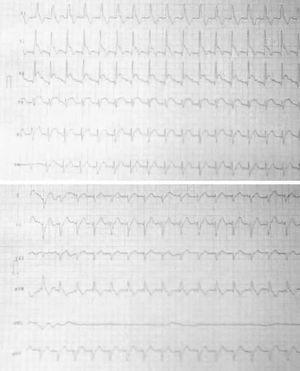

Ante la contraindicación relativa de la fibrinólisis en este contexto, se decidió la realización de un cateterismo cardíaco. En éste se objetivó arteria descendente anterior con una estenosis proximal inferior al 30%, con contenido trombótico y un flujo TIMI III (trombolysis in myocardial infarction). No se observaron lesiones en otros vasos, y la fracción de eyección ventricular fue normal. Asimismo, se evidenció una hipocinesia anterior (fig. 2).

Figura 2. Coronariografía en la que se observa la arteria descendente anterior proximal con contenido trombótico pero con buen flujo distal.

Dada la respuesta positiva eléctrica y clínica al tratamiento médico y los hallazgos de la coronariografía, se decidió no intervenir en un primer momento y observar la evolución.